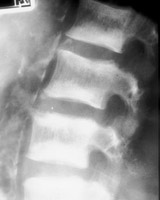

Roentgenographic appearance of increased density in the upper and lower zones of the vertebral body in a striated appearance. The pattern was similar to the alternating colors of the rugby player’s jersey design popular at the time of the description of this entity. Rugger Jersey spine is typically reserved for secondary hyperparathyroidism.

- Click on the image for a larger versionA - Click on the image for a larger versionB